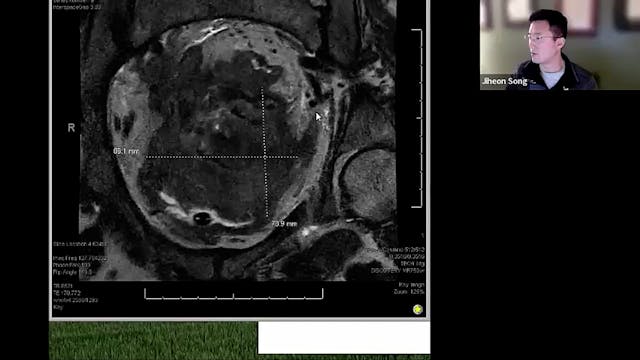

04/18/2024 - Dr. Christine Fisher - Radiation Oncology - GYN

Chartrounds US - GYN